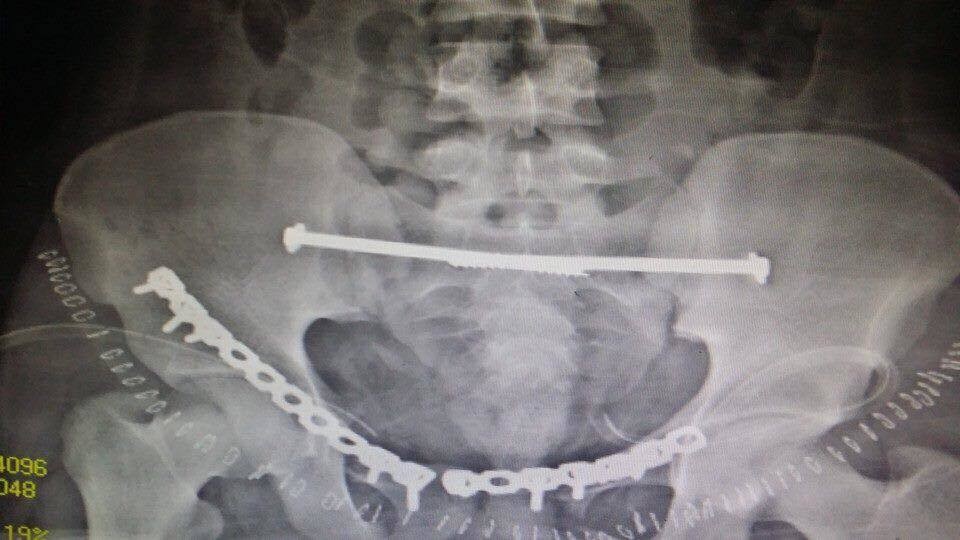

انقاذ مريض تعرض لكسور متعددة بالحوض

انقذ مريض تعرض لكسور متعددة بالحوض

المستشفي السعودي الالماني بالرياض يواصل اجراء جراحات الحوض المعقده بنجاح لافت

يواصل المستشفي السعودي الالماني بالرياض اجراء جراحات الحوض المعقدة بنجاح كبير ، جعله من المقاصد الطبية المتميزة ،تعد جراحات الحوض من الجراحات المعقده ، التى تعتبر تحديا كبيرا يواجه جراحى العظام، حيث تتطلب مجهودا كبيرا ومهارة من جراح العظام والفريق الطبى المعاون له . وتعتبر المستشفى السعودى الالمانى بالرياض احد المستشفيات الرائدة ذات السمعة الطيبه فى هذا النوع من الجراحات خاصه وفى جراحه العظام بصوره عامه.

وكان قد حضر مريض الى طوارىء المستشفى اثر تعرضه لحادث سياره ،وكانت حالته العامه صعبه للغايه . وعلى الفور تم عمل الإسعافات اللازمه للمريض وتم دخوله على الفور للعناية المركزه و عمل جميع الفحوصات اللازمه من اشعات عاديه وتلفزيونية ومقطعيه ، حيث تبين وجود كسور متعدده وانفتاح فى الحوض مع وجود نزيف حاد بالحوض قد يؤثر على حياه المريض . وعلى الفور تم إيقاف النزيف بواسطه فريق متكامل من أطباء الاشعه التداخليه.

وبعد استقرار الحاله العامه للمريض ، تمت مناظره الكسور الموجودة من قبل الدكتور محمد فوزي رئيس قسم العظام ، والذى قرر بإجراء تدخل جراحى لفتح وتثبيت الكسور المتعددة بالحوض بواسطه شرائح ومسامير معينه .

وبالفعل تم عمل التحاليل اللازمه ، و دخول المريض لغرفه العمليات ، حيث تم فتح وتثبيت الكسور . وبحمد الله وتوفيقه تمت العمليات جميعها بالحوض فى جلسه واحده وبنجاح تام ومكث المريض بالمستشفى لعده ايام بعد الجراحة للاطمئنان على الحاله العامه والغيار المستمر على الجروح . وبحمد الله خرج المريض من المستشفى بحاله جيده واستمر فى المتابعة بالعياده الخارجيه بقسم العظام بالمستشفى حتى تمكن من المشى بصوره منتظمة وطبيعية .